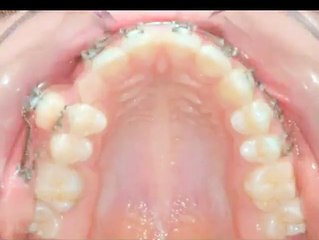

20 yaş dişleri neden çekilmelidir?